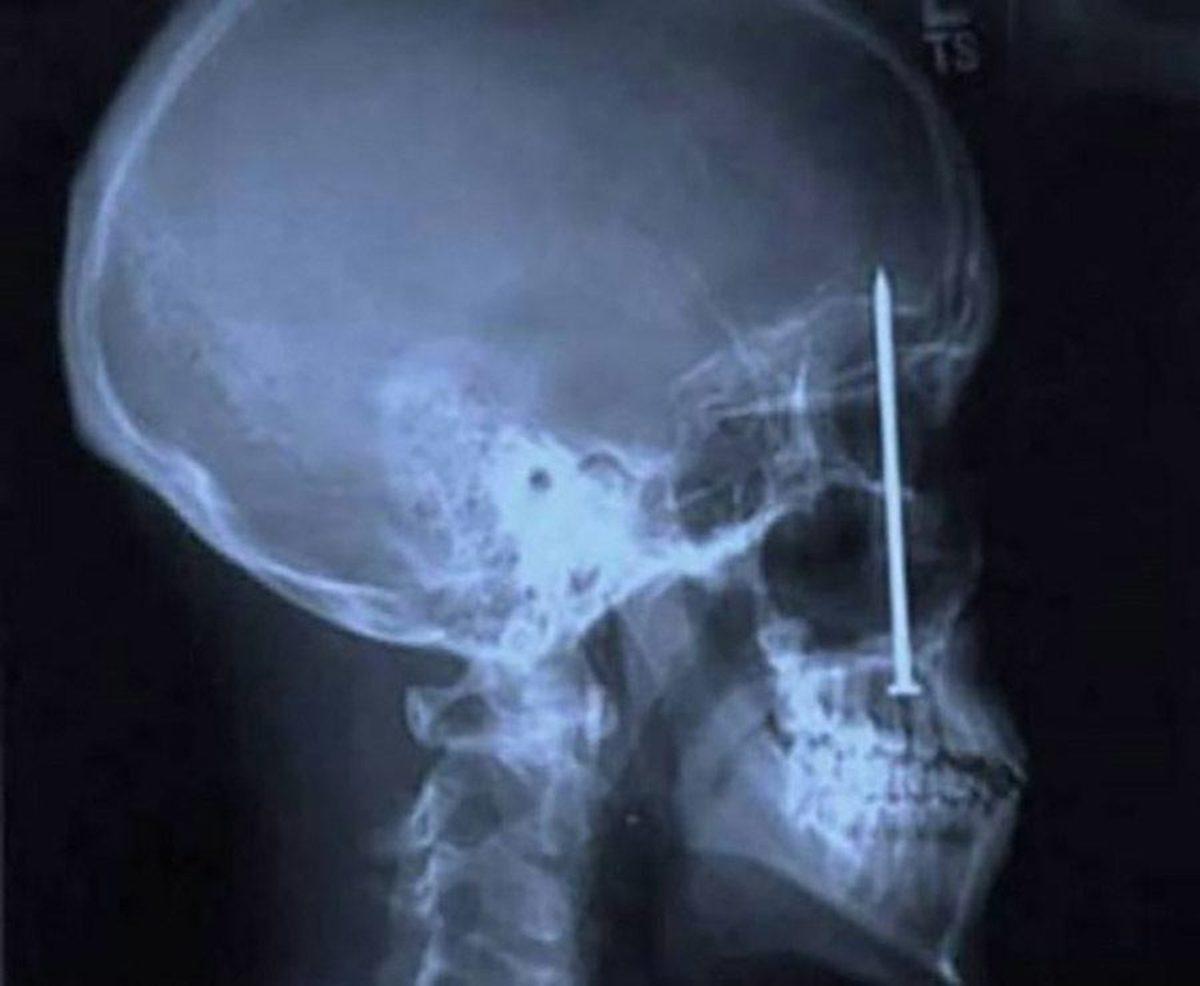

- 3 yaşındaki çocuğun gözüne saplanan bir vida.

Babası çimleri biçerken yerdeki vida fırlayarak çocuğa isabet etmiş. Neyse ki sadece yaralanmayla atlatmış.

- Çin'in Vuhan şehrindeki bu çocuk, burnuna soktuğu yemek çubuğuyla beynini delmiş.

- Pakistan'da yaşayan bu kadının kafasına 5 cm'lik çivi girmesi her ne kadar ilginç olsa da bunun yaşanma sebebi çok daha ilginç.

3 kızı olan bu kadın, kocasının erkek çocuk istemesi üzerine hocaya gidiyor ve bu hoca, bebeğin erkek olması için kadının kafasına çivi çakıyor!